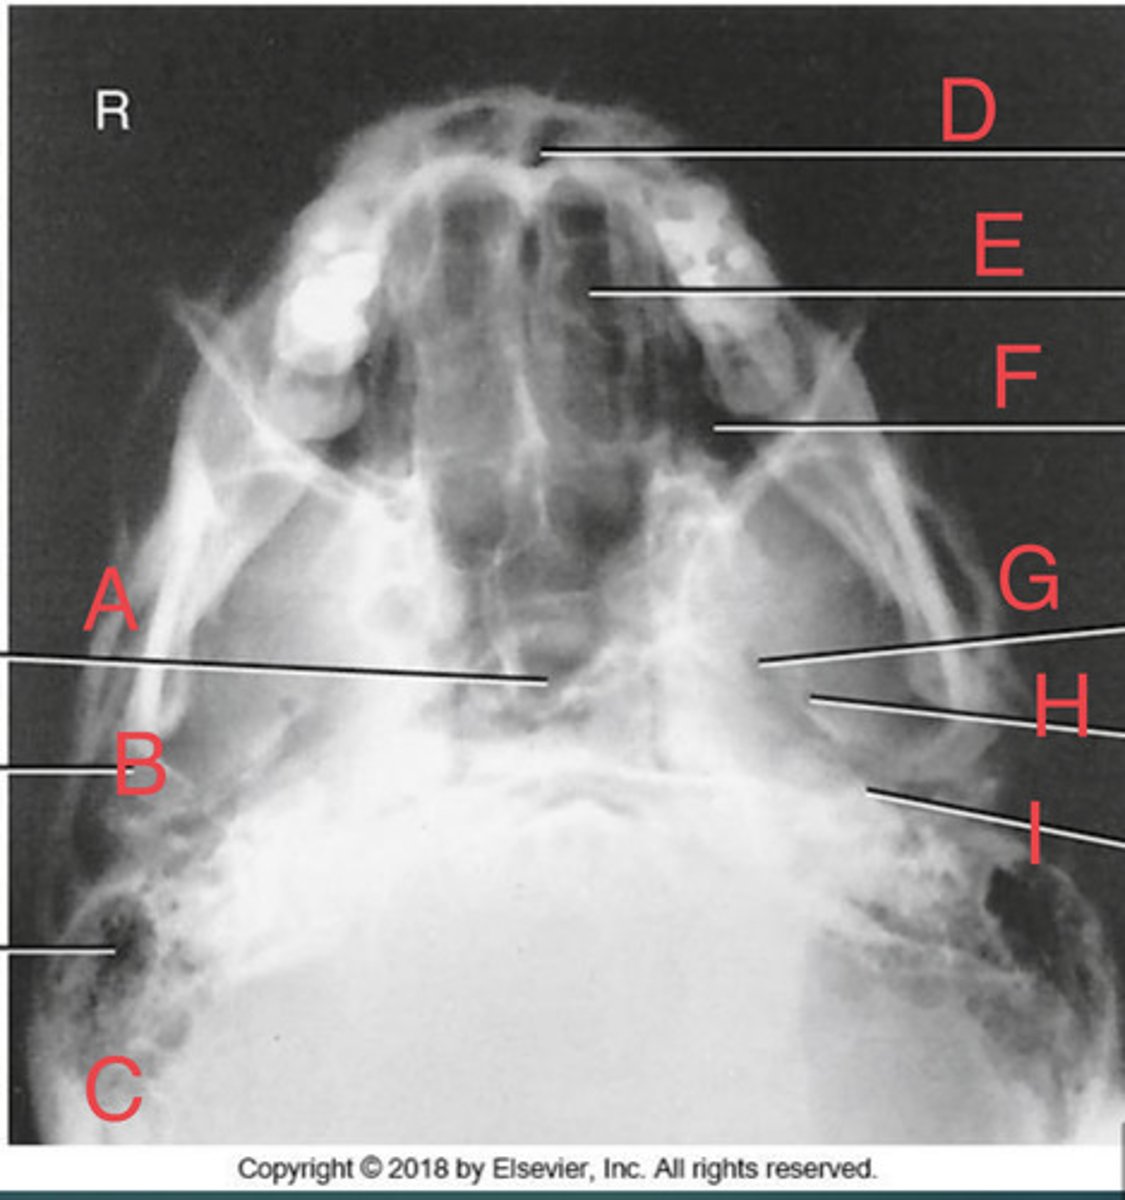

SMV sinuses

What position?

Sphenoid sinus of sphenoid bone

A.

R mandibular condyle of mandible

B.

R Mastoid air cells of temporal bone

C.

Nasal fossa

D.

L. Ethmoid sinus of ethmoid bone

E.

L maxillary sinus of maxilla

F.

L foramen ovale of sphenoid bone

G.

foramen spinosum of sphenoid bone

H.